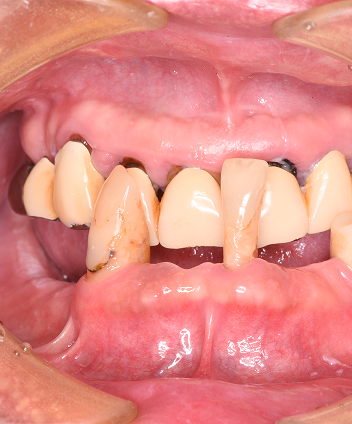

デジタル精密設計×審美再建“美しく噛めるAll-on-4”

Point03

デジタル精密設計×審美再建

“美しく噛めるAll-on-4”

3DフェイススキャンやCT、口腔内スキャナーによる完全デジタルのフル設計と診断で歯と口元だけでなくお顔のバランスにも配慮した設計を提供しています。また術後のメンテナンスと清掃性を大切にして炎症や口臭トラブルを軽減します。